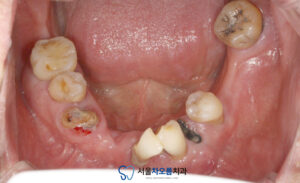

환자분께서는

아래쪽 치아의 상실된 부분이 많고

남아있는 치아도 온전치 않아

식사하기 불편하시다며

내원해주셨습니다.

확인해보니,

아래쪽 치아들의 상실된 부분도 있고,

남아있는 치아들의 예후도

안좋았는데요.

오른쪽 아래 큰 어금니는

뿌리 하방으로 염증이

크게 잡혀있었습니다.

25.03.21

관리가 잘 되지 않아

치석이 많이 쌓여 있었고,

여러 부위에서 충치도

깊게 진행된 상태였습니다.